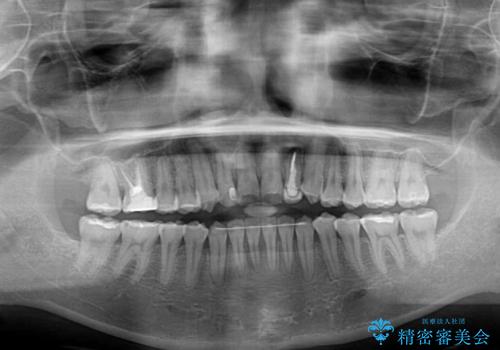

開咬を治す インビザラインによる矯正治療

- 上下前歯の開咬を気にして来院された患者様です。

開咬はインビザラインを用いると有意に改善ができるため、インビザラインによる矯正治療を行うこととしました。